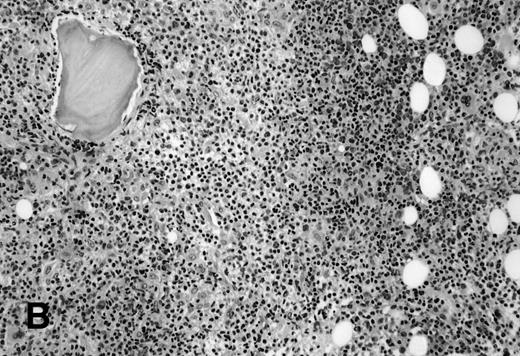

It is the remaining 15 cases that deserve additional description. Ten cases demonstrated morphologic features of lymphoma on the BM biopsy specimen and were confirmed by immunohistochemical staining, but had a polyclonal B-cell immunophenotypic pattern. Subgating based on cell size and backgating with CD19 or other antibodies failed to identify a monoclonal or abnormal B-cell population. κ/λ ratios ranged from 0.20 to 1.8:1 in these 10 cases. Five of the 10 cases were from patients with follicular lymphoma, predominantly small cleaved type, and 5 were from patients with large-cell lymphoma (Fig 1). One of the latter 5 patients with large-cell lymphoma had a discordant BM morphology with primarily a small, cleaved cell infiltrate seen in the BM sections. In addition to morphologic features indicative of lymphoma, all 10 cases demonstrated a prominent CD20+, lymphomatous infiltrate by immunohistochemistry on paraffin sections of the marrow biopsies. The extent of involvement by lymphoma in these cases was quite variable, with 4 showing small, focal, paratrabecular patterns of infiltration; 4 showing less than 20% involvement in a random, nodular pattern; and 2 cases with single, albeit relatively large, foci. It seems reasonable to conclude that the discordance seen in these 10 cases may be ascribed to either variation in sampling between the aspirate and biopsy, the minimal marrow disease seen in some biopsies and not represented in the aspirate specimen, or failure to aspirate the diagnostic cells due to reticulin fibrosis that can be associated with a lymphomatous infiltrate.16 28

(A) BM biopsy showing a paratrabecular lymphoid infiltrate of atypical lymphoid cells, diagnostic of involvement by malignant lymphoma and confirmed by CD20+immunohistochemical staining. A lymph node biopsy showed a follicular lymphoma. Flow cytometric studies demonstrated polyclonal B cells with no monoclonal B-cell population identified (H&E; original magnification × 400). (B) BM biopsy showing a nodular lymphoid infiltrate of atypical, large lymphoid cells, diagnostic of involvement by malignant lymphoma and confirmed by CD20+ immunohistochemical staining. A lymph node biopsy showed a large-cell lymphoma. Flow cytometric studies of the marrow aspirate demonstrated polyclonal B cells with no monoclonal B-cell population identified (H&E; original magnification ×400).